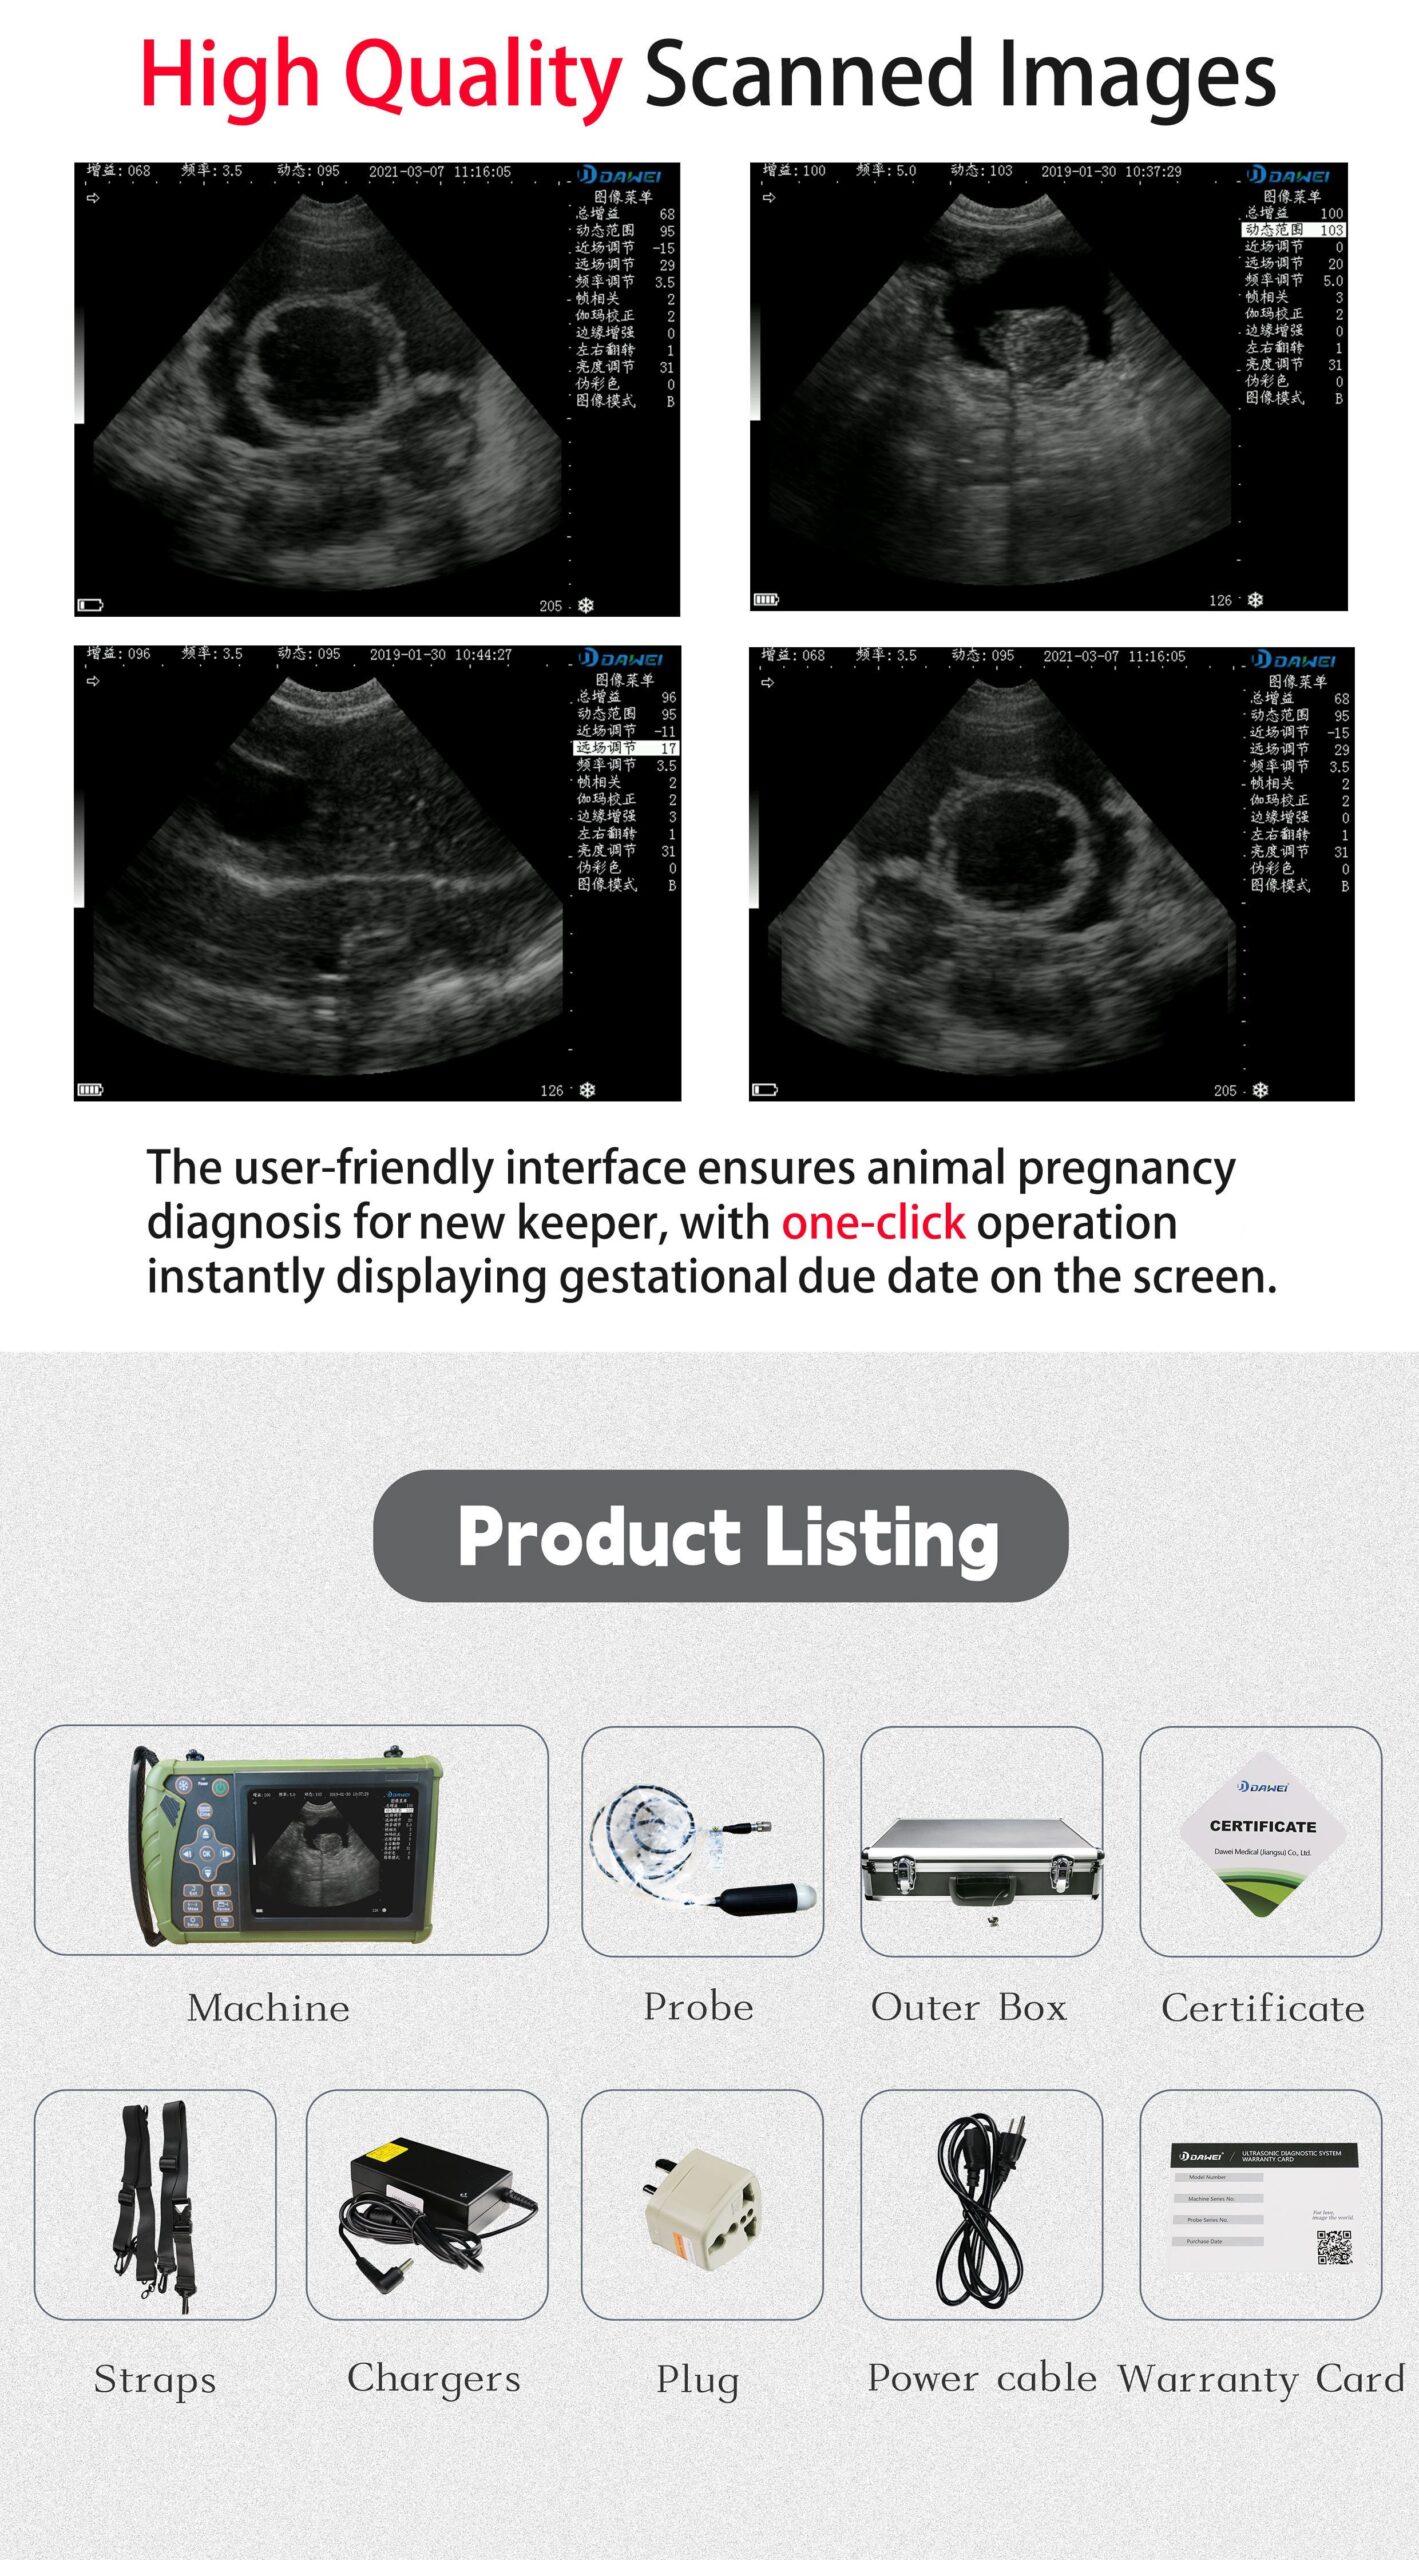

3.5MHz Probe: Ideal For Ultrasound Imaging And Pregnancy Testing Of Medium-sized Animals Such As Pigs, Sheep, Dogs, Etc

DAWEI-S0 Is A Portable Veterinary Ultrasound (B-ultrasound) Diagnostic Instrument. Its Superior Product Performance And Ergonomic Handheld Design Bring More Convenience To Users During Testing.